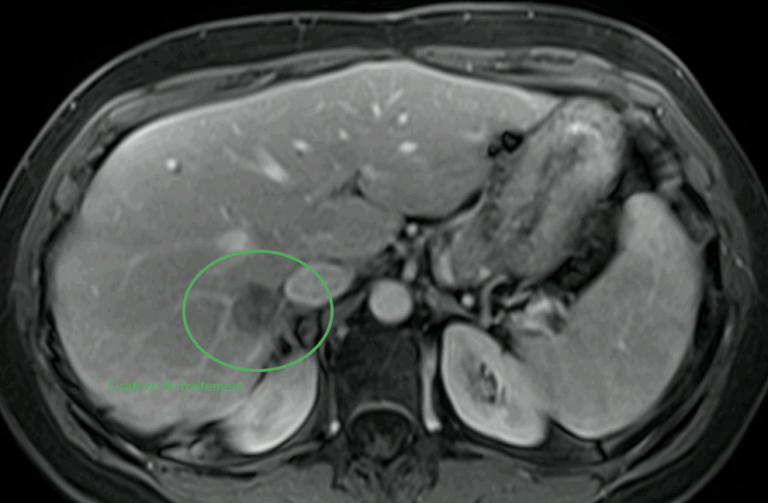

Traitement hépatique par micro-ondes

Dans un second temps, la métastase hépatique est traitée par thermoablation micro-ondes, avec protection des organes voisins grâce à une technique d’hydrodissection.

En images

Images du traitement des organes (poumon et foie) avant, pendant et après le traitement.